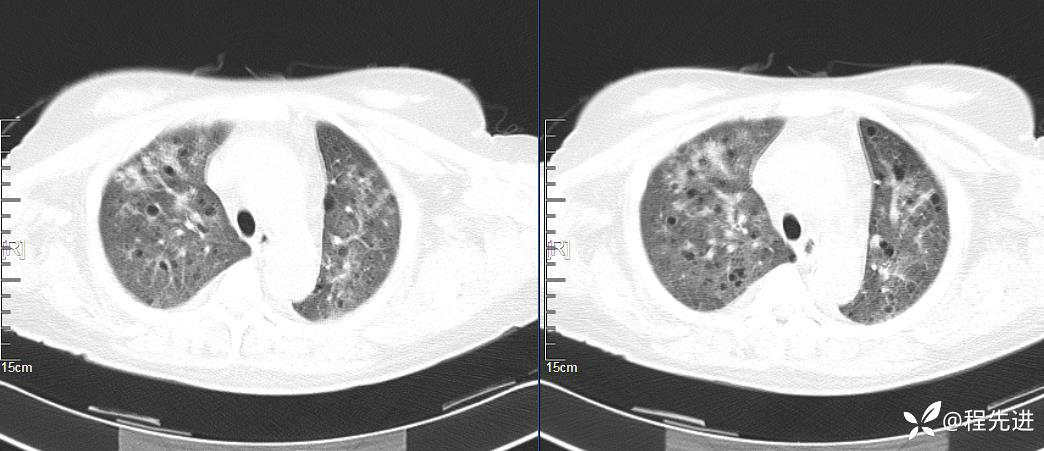

CT平扫(纵隔窗无特殊,就不上传了):

2、本例肺气囊分布有什么特点?肺气囊有无小叶核心?有没有间质纤维化及伴发结节?